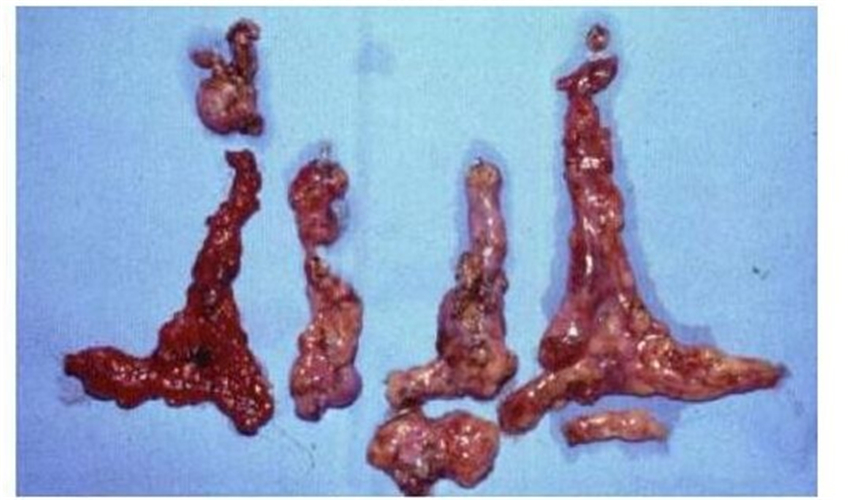

切除的甲狀腺癌

髓養甲狀腺癌伴淋巴轉移

巨大甲狀腺癌